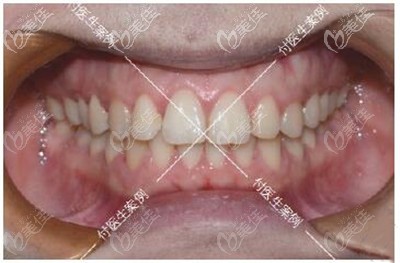

術(shù)后照片:

深覆合牙齒矯正前后牙齒效果對比

具體的治療過程是,因為本身的牙齒問題不大,所以我戴上牙套后沒幾個月牙齒就排齊了,差不多一年多的時間都是在調(diào)整咬合吧,牙齒矯正過程真的酸爽,這里安利一個小技巧,在牙齒矯正期間一定要好好刷牙,要不容易黑三角,而且做好牙齒清潔后,會發(fā)現(xiàn)比以前刷牙干凈好多。

我做牙齒矯正一共花了差不多500多天,看我矯正后的效果,牙齒咬合調(diào)整好了,之前反頜的牙齒也歸隊了,重點是沒想要深覆合做牙齒矯正真的會對臉型有影響!

我現(xiàn)在下巴出來了,笑起來更舒展了,再也不怕會露牙齦了。身邊的朋友多懷疑我去做了整形,問我是不是悄咪咪的墊下巴了!哈哈,反正這個矯正效果我真的很滿意,現(xiàn)在的側(cè)面弧度我真的愛了。